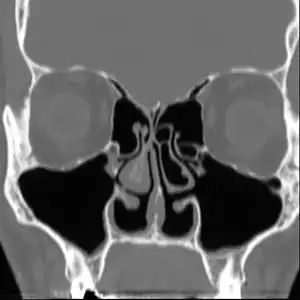

Altered nasal anatomy after bilateral subtotal inferior turbinectomy, the removal of most turbinate tissue.